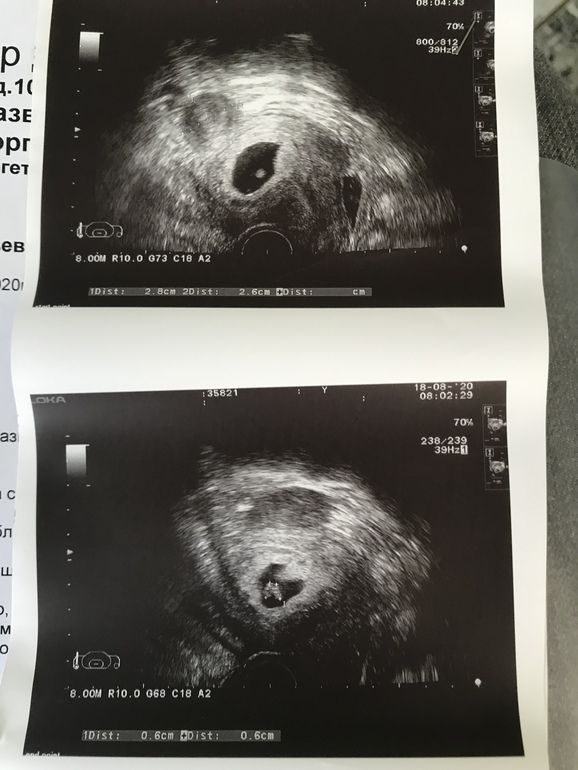

Внутриутробное развитие двойни/тройниЭКО Беременность (6,4 по месячным). Подсаживали 2 эмбриона, но на втором узи на 28 дпп обнаружили два эмбриона в одном пя. То есть один прижился и поделился!! И при этом ОДИН жм!!! Это норм? Посмотрите, пожалуйста узи!!! Беременность первая. Я очень боюсь!

Мира, это до сих пор не известно)) вскоре после этого УЗИ смотрели ещё два врача и видели только одного))